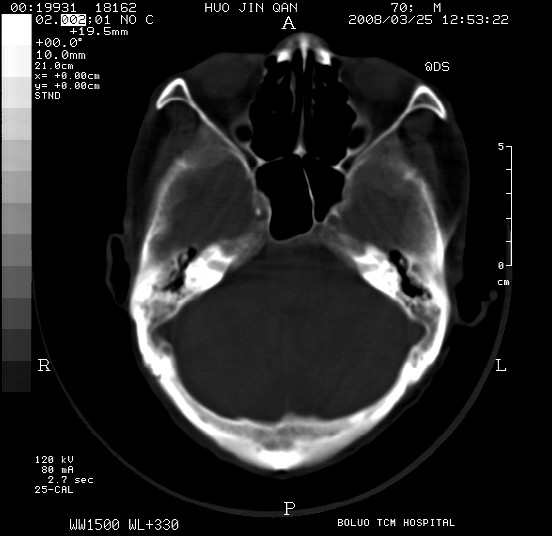

以下是引用随光逐影在2008-3-25 20:15:00的发言:[br]双侧额颞顶部亚急性(或慢性)硬膜下血肿。

以下是引用liuyue在2008-3-26 18:57:00的发言:[br]以下是引用随光逐影在2008-3-25 20:15:00的发言:[br]双侧额颞顶部亚急性(或慢性)硬膜下血肿。 [br]支持![br]可以无明显外伤病史,老年人可以在激烈摇晃或轻微头部碰创头部时,发生硬膜下出血.